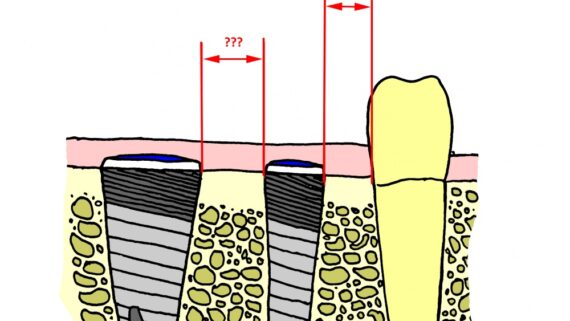

Ее объем, как мы видим, небольшой, использовать его для ПРАВИЛЬНОЙ установки импланта нереально. Почему выделил слово «ПРАВИЛЬНОЙ»? Потому что некоторые типы имплантационных систем позволяют установить имплантат хоть куда, хоть в какой объем кости, если очень хочется, конечно. Но ведь у нас нет задачи «воткнуть» имплантат всеми правдами и неправдами, верно? Комплексная цель лечения — воссоздание полноценно функционального зуба со всеми окружающими тканями. Чем мы, собственно, и занимаемся.

По существующим правилам, при установке импланта в области фронтальной группы зубов, его ось должна выходить на небную поверхность коронки или режущий край. Чего мы и добиваемся, контролируя процесс с помощью пинов.

Я планирую установить имплантат Dentsply Friadent XiVE диаметром 3.8 и длиной 13 мм. Это оптимальный размер импланта для протезирования боковых резцов.

Убираем имплантодержатель. Обратите внимание, что полированная фаска вокруг шейки импланта находится над уровнем костной ткани. Чрезмерное погружение импланта — весьма распространенная имплантологическая ошибка.

Разумеется, чтобы зафиксировать на имплантат коронку, необходимо его открыть. Затем,дождаться эпителизации десны вокруг его соединительной части. Для этого используются формирователи десны: